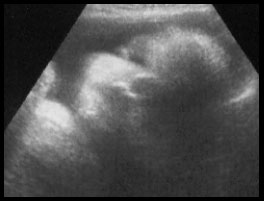

Dr. Appointment Day. You'll have to visit the appointment page to find out more, but I'll post a little picture here for you.